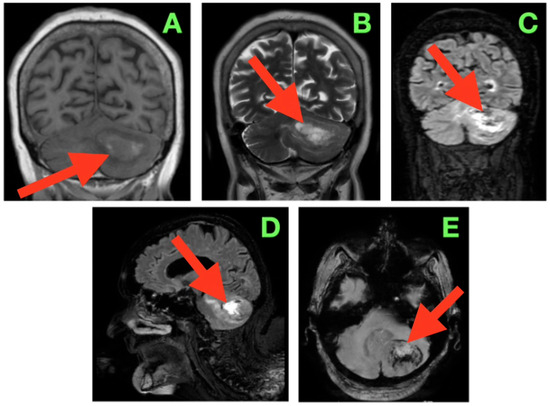

Advanced neuroimaging approaches are being used as valuable additional tools in characterizing brain lesions alongside conventional imaging techniques. The importance of advanced neuroimaging approaches is that they can provide information regarding the underlying pathophysiology of various brain lesions. Currently, both computed tomography (CT) and magnetic resonance imaging (MRI) include modern neuroimaging techniques, like dual-energy CT, photon-counting CT, perfusion MRI, functional MRI, diffusion-weighted MRI, diffusion tensor imaging, MRI spectroscopy, and MRI fingerprinting. Advanced approaches like radiomics analysis applied to CT and MRI images are increasingly being used for brain lesion characterization. Combining advanced neuroimaging approaches along with artificial intelligence techniques such as machine learning and deep learning algorithms will further promote and accelerate the adaptation of advanced neuroimaging methods in routine clinical neuroimaging. This Special Issue, entitled "Brain/Neuroimaging 2025", will include the application of advanced neuroimaging approaches for the characterization of brain lesions (tumors, demyelinating changes, ischemic stroke, hemorrhage, and infectious lesions) and neurodegenerative disorders, as well as the monitoring of treatment-induced brain lesions.